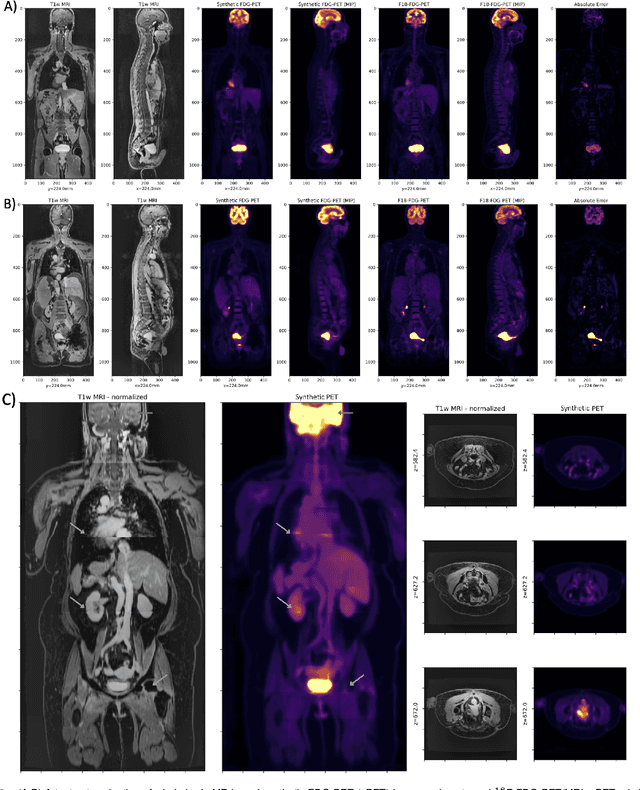

Abstract:Historically, patient datasets have been used to develop and validate various reconstruction algorithms for PET/MRI and PET/CT. To enable such algorithm development, without the need for acquiring hundreds of patient exams, in this paper we demonstrate a deep learning technique to generate synthetic but realistic whole-body PET sinograms from abundantly-available whole-body MRI. Specifically, we use a dataset of 56 $^{18}$F-FDG-PET/MRI exams to train a 3D residual UNet to predict physiologic PET uptake from whole-body T1-weighted MRI. In training we implemented a balanced loss function to generate realistic uptake across a large dynamic range and computed losses along tomographic lines of response to mimic the PET acquisition. The predicted PET images are forward projected to produce synthetic PET time-of-flight (ToF) sinograms that can be used with vendor-provided PET reconstruction algorithms, including using CT-based attenuation correction (CTAC) and MR-based attenuation correction (MRAC). The resulting synthetic data recapitulates physiologic $^{18}$F-FDG uptake, e.g. high uptake localized to the brain and bladder, as well as uptake in liver, kidneys, heart and muscle. To simulate abnormalities with high uptake, we also insert synthetic lesions. We demonstrate that this synthetic PET data can be used interchangeably with real PET data for the PET quantification task of comparing CT and MR-based attenuation correction methods, achieving $\leq 7.6\%$ error in mean-SUV compared to using real data. These results together show that the proposed synthetic PET data pipeline can be reasonably used for development, evaluation, and validation of PET/MRI reconstruction methods.